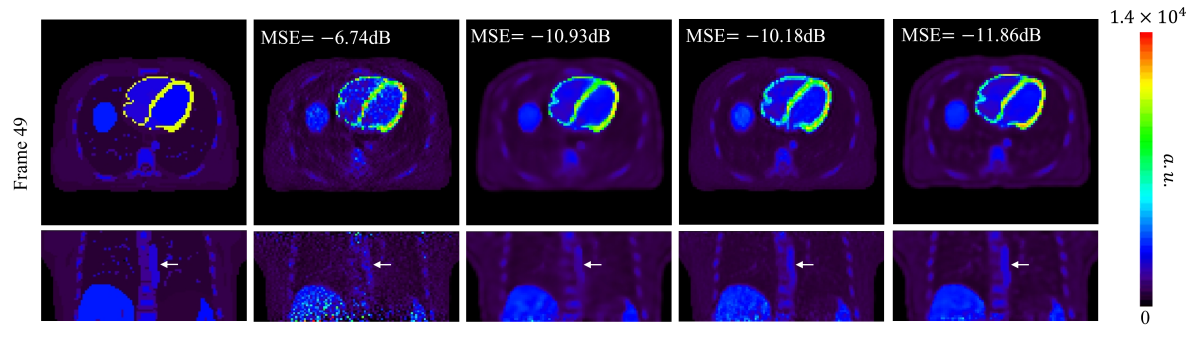

Fig. 9 shows the true 3D activity images and reconstructed images at iteration 60 by different reconstruction methods for frame 6 (early 10-s frame, low-count level) and frame 49 (late 5-min frame, high-count level). The proposed neural KEM achieved the lowest image MSE for both frames.

Fig. 10(a) shows the plots of image MSE for all frames reconstructed by different methods with 60 iterations. The two kernel-based methods (regular KEM and neural KEM) demonstrated a substantial improvement as compared to the ML-EM and DIP methods. The neural KEM was further better than the regular KEM particularly for those low-count frames.